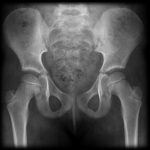

Tuổi xương là khái niệm dùng để đánh giá mức độ trưởng thành của hệ xương, dựa vào nhân cốt hóa xương chi. Trong giai đoạn phát triển từ một đứa trẻ sơ sinh cho đến độ tuổi thanh thiếu niên, có một sự tương quan giữa tuổi xương so với tuổi khai sinh, thường là không quá 10%. Cốt hóa là tiến trình sụn ở trẻ sơ sinh phát triển dần thành xương hoàn chỉnh ở thanh thiếu niên trưởng thành. Các điểm cốt hóa của xương cũng là quá trình phân bào ở sụn tăng trưởng, nhằm giúp xương dài ra. Theo trình tự nhất định, thời điểm xuất hiện và mức độ cốt hóa của các điểm cốt hóa đầu xương sẽ tương ứng với tuổi đời thực khác nhau của trẻ…